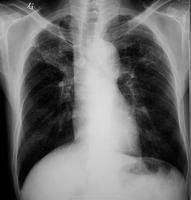

5.膈肌和肋膈角:一般右肋膈頂在第五肋前端至第六肋前間水平,由於右側有肝臟的存在,右膈頂通常要比左側高一到兩厘米。意義:胸腔或腹腔壓力的改變可以改變膈肌的位置如氣胸時膈位置可以壓低;膈神經麻痹出現矛盾呼吸。正常的肋膈角是銳利的,如果肋膈角變鈍則有胸腔有積液或積血存在,如何來大體判斷積液的量呢?一般說肋膈角變鈍:積液300ml;肋膈角閉鎖: 500ml。

一般右肋膈頂在第五肋前端至第六肋前間水平,由於右側有肝臟的存在,右膈頂通常要比左側高一到兩厘米。意義:胸腔或腹腔壓力的改變可以改變膈肌的位置如氣胸時膈位置可以壓低;膈神經麻痹出現矛盾呼吸。正常的肋膈角是銳利的,如果肋膈角變鈍則有胸腔有積液或積血存在,那我們如何來大體判斷積液的量呢?一般說肋膈角變鈍:積液300ml;肋膈角閉鎖:500ml。乳頭